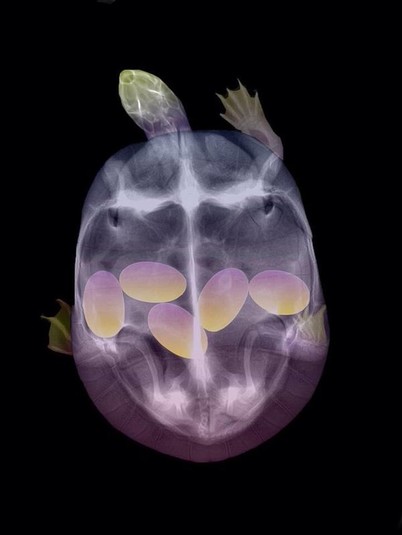

15 удивительных рентгеновских снимков беременных животных

Специалисты, которые по долгу своей работы наблюдают животных, готовых принести потомство, поделились этими удивительными рентгеновскими и ультразвуковыми снимками.